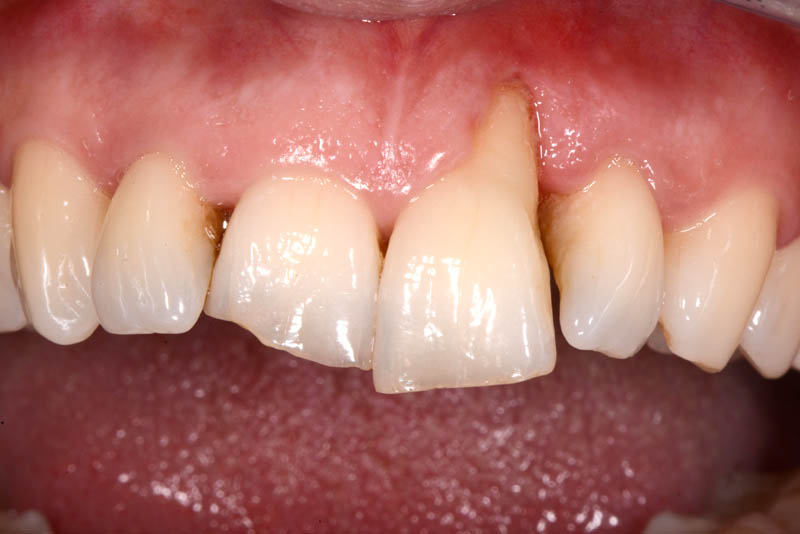

The rehabilitation of this periodontally compromised tooth required a multidisciplinary approach, combining both periodontal and orthodontic treatments.

Following an initial phase of non-surgical periodontal therapy aimed at removing subgingival calculus, Dr. Anna Mariniello performed both upper and lower alignment using a lingual, non-bracket orthodontic technique, employing active retainers applied to the lingual surfaces of the teeth.

At the end of the orthodontic treatment, a coronally advanced flap was performed according to the De Sanctis and Zucchelli technique, involving papilla preservation and connective tissue grafting, to restore the gingival contour and the papilla between teeth 21 and 22.